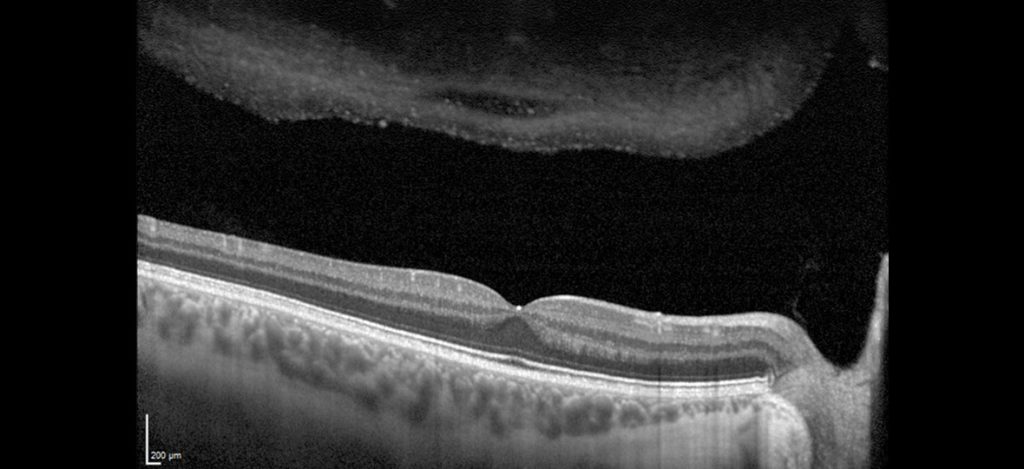

8.Módulo de Angiografia OCT

Imagem vascular não invasiva

O Módulo de Angiografia OCT SPECTRALIS® oferece imagens de OCTA de alta resolução, com uma resolução lateral de 5,7 μm/pix. Combinado com a precisão do TruTrack Active Eye Tracking, o módulo OCTA permite visualizar redes capilares finas com grande detalhe.

A resolução axial de 3,9 μm/pixel permite a segmentação de todos os quatro plexos vasculares da retina validados histologicamente. Lâminas personalizadas dentro dos plexos vasculares superficial e profundo oferecem uma avaliação clínica mais abrangente.

A ferramenta de remoção de artefatos de projeção (PAR) utiliza informações do plexo vascular superficial para remover artefatos das imagens OCTA. Isso possibilita uma visualização mais precisa da estrutura vascular e das patologias.

• Campo de visão flexível

• Remoção de Artefatos de Projeção (PAR)

• Angiografia Hibrida

• Imagem Multimodal com OCTA